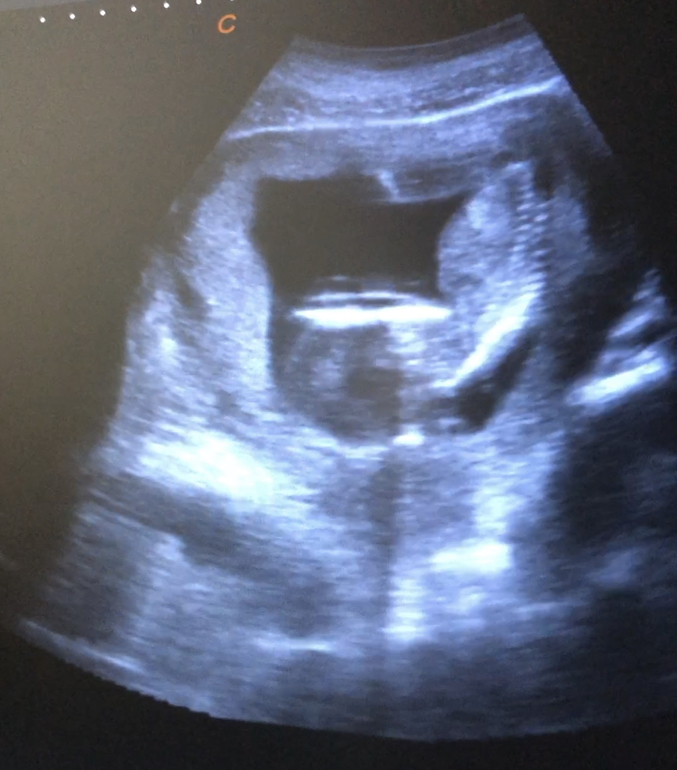

Вот, единственное, кто знает из вас, девчонки, у всех на этом сроке детки как будто в три погибели согнуты?

Мне не понравилось что голова так сильно к груди прижата, или это норма? Успокойте пожалуйста

Вот фото положения дитя